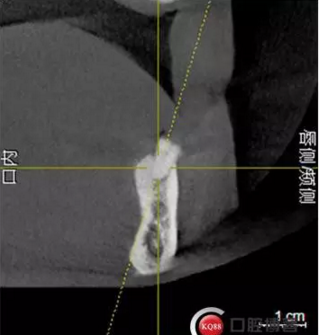

檢查:上頜無(wú)牙頜假牙穩(wěn)定性尚可,下頜3435364243殘根;33殘冠1-2度松動(dòng),其他牙齒缺失;CBCT檢查:下頜牙槽骨前牙區(qū)骨高度足,后牙區(qū)骨高度最低為8mm,骨寬度足。

2)術(shù)前準(zhǔn)備及手術(shù)過(guò)程,測(cè)量血壓及血糖,簽種植知情同意書(shū);嚴(yán)格遵循無(wú)菌操作,局麻下采用微創(chuàng)技術(shù)于323436分別植入osstem4.0X10,4.0X10,4.5X7; 434446分別植入osstem4.0X1O,4.0X10,4.5X7.初期穩(wěn)定性均達(dá)到了35N.CM以上;嚴(yán)密縫合,止血,種植體位點(diǎn)和方向與設(shè)計(jì)一致。